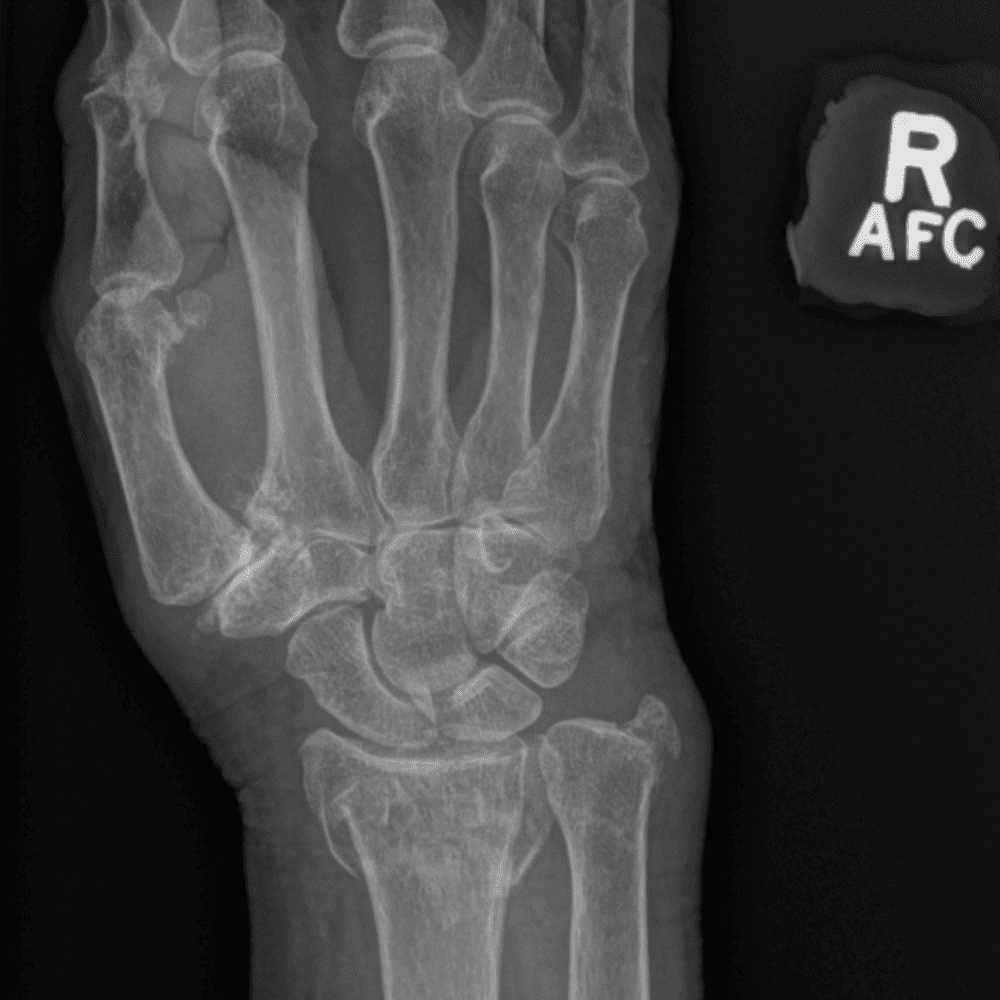

Simuliert den Dienst durch subtile oder schwierige Fälle und einige Normalbefunde.

30 Fälle